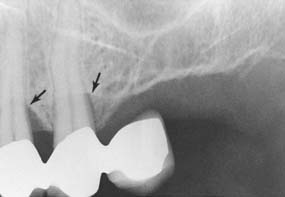

Fig. 32-30 Osseous defects (arrows) within 2 years of the placement of this partial fixed dental prosthesis.

(Courtesy of Dr. J. Keene.)